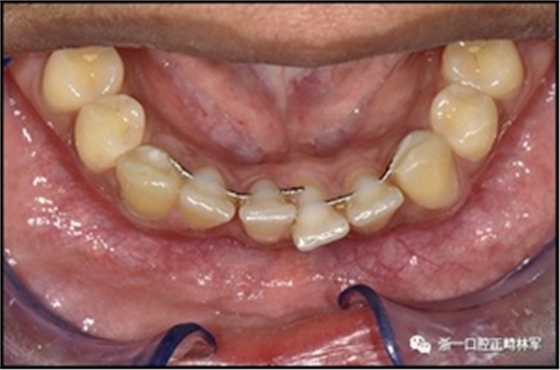

當(dāng)弓絲斷裂時(shí),由于意外的牙齒移動(dòng)更可能導(dǎo)致牙齒排列整齊性喪失。這似乎最可能發(fā)生在較小直徑的極軟弓絲上(圖1),但它也會(huì)在粘合每顆牙齒的小柔性螺旋弓絲上發(fā)生。弓絲斷裂可能導(dǎo)致根本無(wú)法保持當(dāng)弓絲部分缺失時(shí),或可能導(dǎo)致由剩余弓絲部分造成的個(gè)別牙齒移動(dòng)(圖2)。

圖1.中間切牙間極軟弓絲斷裂,導(dǎo)致2段牙齒移動(dòng)。注意左側(cè)尖牙和左側(cè)中切牙的扭矩在相反的方向。

圖2.極軟弓絲,一半缺失,間隙開(kāi)放和牙齒移動(dòng)。很可能右側(cè)牙齒在最后失去之前被該側(cè)的弓絲段移動(dòng)。